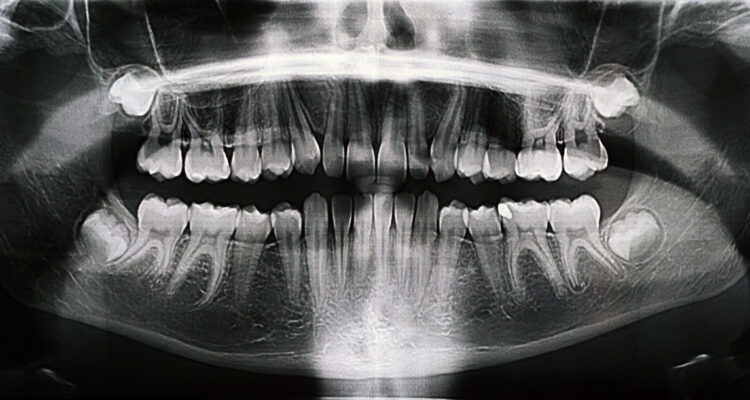

LA IMPORTANCIA DE LA SALUD BUCAL EN LA PREVENCIÓN Y DIAGNÓSTICO OPORTUNO DE ENFERMEDADES SISTÉMICAS